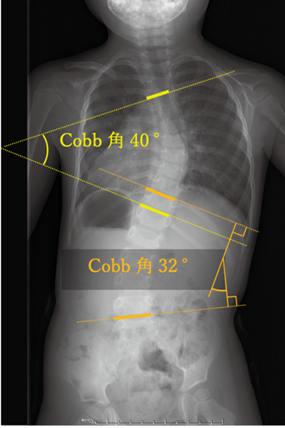

図:Cobb角の計測方法:立位単純X線で傾きの強い椎体の角度を計測する

X線(レントゲン)検査

側弯症の診断と進行度評価に最も重要な検査です。立位で背骨全体のX線写真を撮影し、弯曲の角度(コブ角)を測定します。これにより、側弯症の有無、湾曲の程度、タイプ、進行度などを正確に評価します。定期的なX線検査は、側弯症の進行をモニタリングするために不可欠です。さらに、腸骨稜部の骨化はRisser signとして骨成熟の指標として有用です。側弯症が進行する時期はgrowth spurt(身長が最も伸びる時期)と重なります。女児の場合は初経の1年前がこの時期にあたります。Risser signや初経の時期を参考にして、側弯症の進行を予測します。

また、側弯症は脊柱が正中より偏位し、主カーブのCobb角が10度以上あるものと定義します。